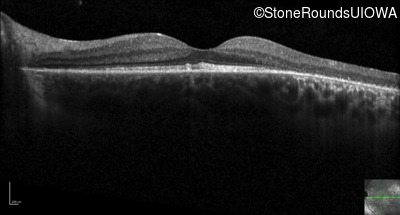

Optical Coherence Tomography - Left - 20/30 +2

Exemplar / OCT Stack

OCT Stack